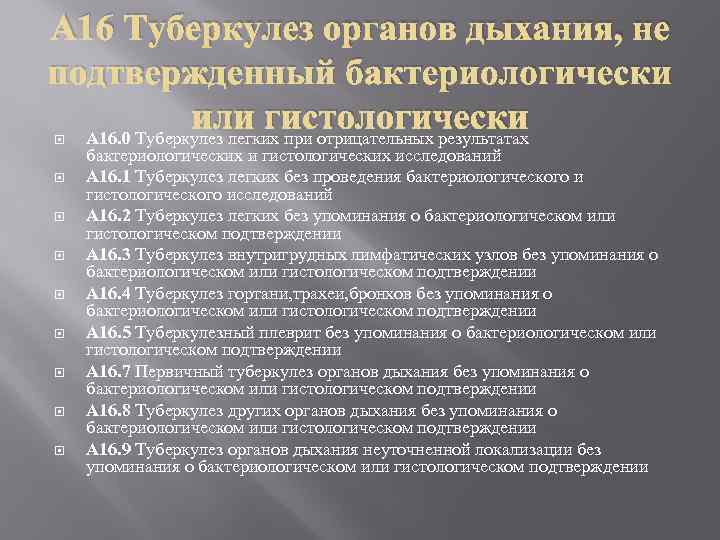

Лечение туберкулеза: Методики химиотерапии

Раздел: Визуальный дайджест